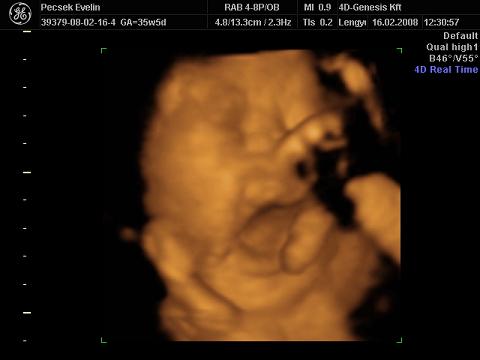

Voltunk 4D-s UH-n is, igaz, hogy 02.16-án (33. héten), de most teszek fel képeket és adatokat a gép hibája miatt

súly: 2211g

BPD: 8,35cm

OFD: 10,62cm

HC:30,3cm (nekem születéskor volt 30cm a fejkörfogatom :shock: )

AC:29,67cm

FL:6,45cm

Liza nőiessége:

ásít, már nagyon únja a banánt :lol: :

itt a nyelvét nyújtogatja:

kezével csikizi a saját kis talpát :lol: :

Liza megmutatta az arcát a végére (egész végig takarta a kezével és lábával, bezzeg a punciját azt nem):